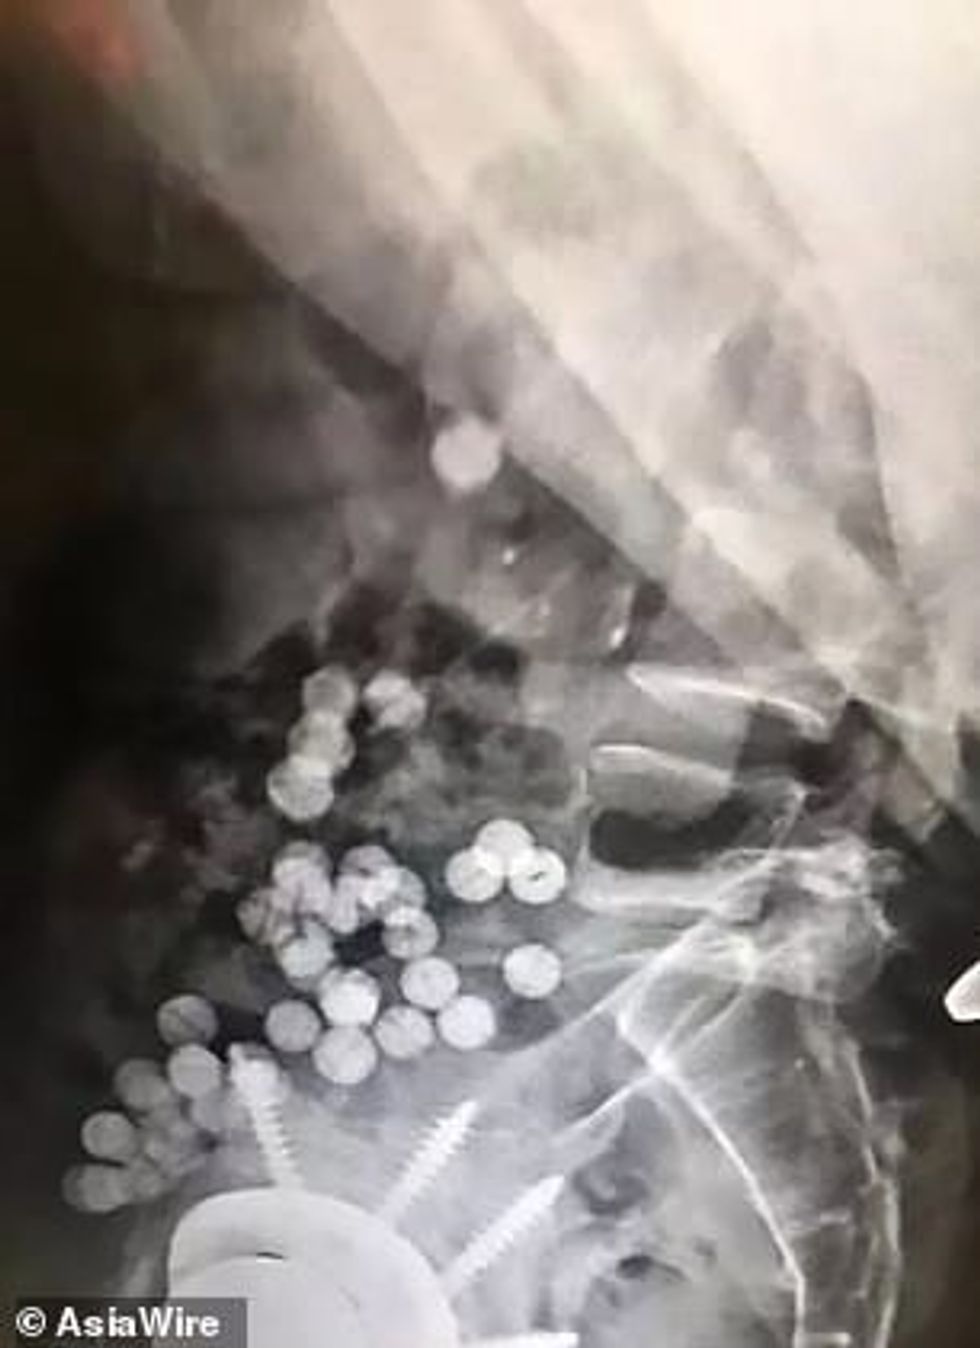

Fotografimi me rreze X, ka treguar se ai ka në bark së paku 40 gurë të zhadit, që besohet se i ka shkëputur nga qaforja.

Atë po e mbajnë nën kontroll, derisa të kryejë nevojën dhe të nxjerrë pjesët e stolisë. /Telegrafi/